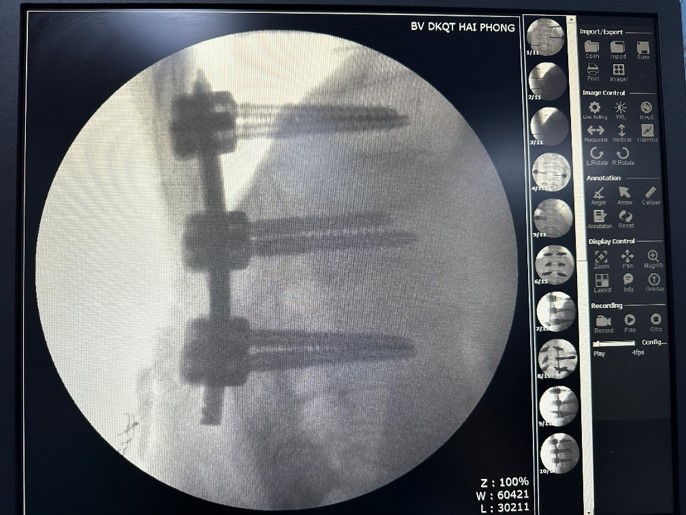

Nhanh chóng, người bệnh được thực hiện phẫu thuật cố định cột sống bản lề ngực thắt lưng bằng phương pháp bắt vít qua da. Ca phẫu thuật thành công, hậu phẫu bệnh nhân ổn định, đau ít hơn so với phẫu thuật mổ mở do vết mổ chỉ là các vết rạch da nhỏ( mổ mở là đường rạch da dài) và không gây tổn thương các cấu trúc dây chằng phía sau cột sống. Ngày thứ 2 sau mổ bệnh nhân đã có thể mặc áo nẹp cột sống hỗ trợ để tập vận động đi lại. Bệnh nhân ra viện sau 5 ngày điều trị.

BSCKI. Nguyễn Mạnh Thuần – Khoa Ngoại chấn thương chỉnh hình – người trực tiếp thực hiện ca phẫu thuật cho biết, cố định cột sống bằng bắt vít qua da là phương pháp điều trị hiệu quả với những tình trạng chấn thương cột sống như ca bệnh trên. Phương pháp này có ưu điểm lớn nhất đó là tối thiểu hóa sự xâm lấn vào cơ thể người bệnh, vì kích thước mở da chỉ bằng với kích thước mà vít đi qua. Nếu như trước đây, người bệnh phải chịu một vết mổ dài gây tổn thương cấu trúc dây chằng phía sau cột sống dẫn đến làm chậm quá trình hồi phục và phục hồi chức năng, thì với phương pháp cố định cột sống bằng bắt vít qua da, thời gian hậu phẫu ngắn, giảm nguy cơ tai biến và đặc biệt hiệu quả của phương pháp cao, đảm bảo cột sống chắc chắn, phục hồi sức khỏe của người bệnh ngay sau chấn thương.